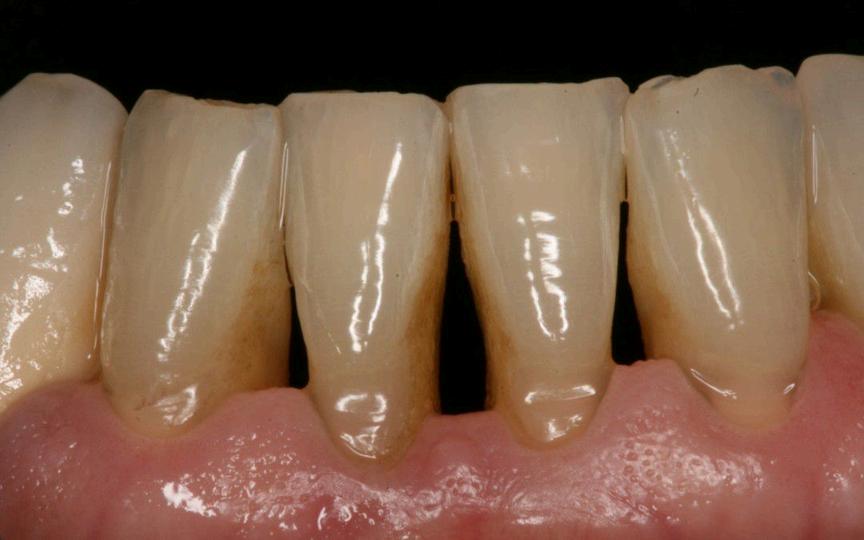

Si no tiene una buena higiene la placa y el sarro se acumulan en la base del diente, esto hace que la encia se inflame y esta misma se distancie de la superficie dentaria dando paso a una bolsa periodontal. Estas se llenan de bacterias provocando infecciones, si estas continuan con el tiempo, al final destruyen los tejidos y el hueso al rededor del mismo, asi perdemos estabilidad y sustencion de nuestro diente.

Sintomas

Encias rojas o inflamadas

Dientes flojos o sencibles

Tratamientos para la periodontitis

Raspado y alisado reticular (limpieza manual por debajo de las encias) junto a enseñanzas de instrucciones de higiene.